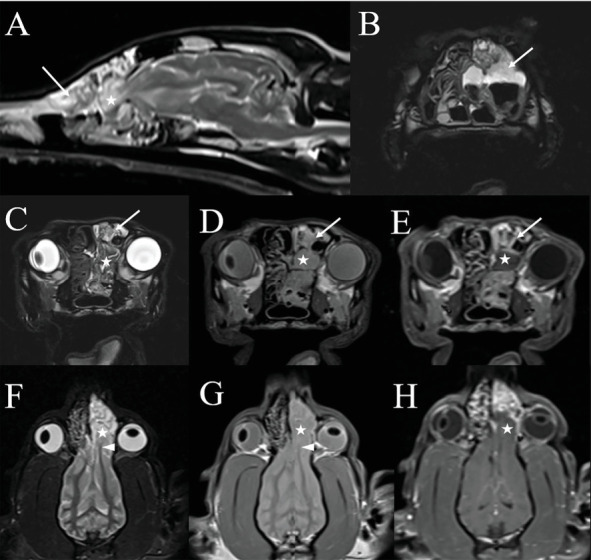

一只4岁雄性阉割混血狗被田纳西大学兽医学院兽医中心收治,以评估单侧鼻分泌物。患者出院已有2个月,在转诊前6周由兽医经验性治疗后,病情由脓性发展为出血性。狗有癫痫发作的历史,从1岁开始,用苯巴比妥控制。头部的计算机断层扫描和磁共振成像诊断为左侧脑膜脑膨出,嗅球延伸至鼻尾通道,伴有曲霉菌病的破坏性鼻炎和额窦炎。进行鼻镜检查以收集诊断样本,清除真菌斑块,并指导克霉唑乳膏的应用。活检显示化脓性鼻炎伴大量曲霉病,真菌培养证实为曲霉属。术后给予短疗程口服泊沙康唑治疗。治疗后4个月出现剧烈呼吸。复查鼻窦镜和鼻镜发现左鼻腔有一个真菌斑块,鼻甲小,充血。反复治疗,临床症状得到缓解。1个月后复查鼻镜未见残留病变。癫痫在第二次治疗后3年复发,由初级保健兽医进行医学处理。这个病例报告描述了一个罕见的病例鼻曲霉病并发脑膜膨出。尽管大筛网板缺损导致脑膜和嗅球暴露,但该患者对反复清创和局部抗真菌治疗耐受良好。3年无复发迹象,此后犬失去随访。

A 4-year-old male castrated mixed breed dog was admitted to the Veterinary Medical Center of the University of Tennessee College of Veterinary Medicine for evaluation of unilateral nasal discharge. Discharge had been present for 2 months, with progression from purulent to hemorrhagic discharge after empiric treatment by the primary veterinarian 6 weeks prior to referral. The dog had a history of seizures starting at 1 year of age that were controlled with phenobarbital. Computed tomography and magnetic resonance imaging of the head yielded diagnoses of a left-sided meningoencephalocele with extension of the olfactory bulb into the caudal nasal passage and destructive rhinitis and frontal sinusitis consistent with aspergillosis. Rhinoscopy was performed to collect diagnostic samples, debride fungal plaques, and guide clotrimazole cream application. Biopsies revealed suppurative rhinitis with abundant aspergillosis, with Aspergillus sp. confirmed on fungal culture. Postoperatively, the patient was treated with a short course of oral posaconazole. Stertorous breathing was noted 4 months following treatment. Recheck sinoscopy and rhinoscopy revealed one fungal plaque in the left nasal cavity and small, hyperemic turbinates. Treatment was repeated, resulting in resolution of clinical signs. Repeat rhinoscopy 1 month later had no evidence of residual disease. Seizures recurred 3 years after the second treatment and were medically managed by the primary care veterinarian. This case report describes a rare case of nasal aspergillosis complicated by a meningoencephalocele. Despite the large cribriform plate defect resulting in exposure of the meninges and olfactory bulb, repeated debridement and topical antifungal treatment were well tolerated by this patient. There was no recurrence in signs for 3 years, after which the dog was lost to follow-up.